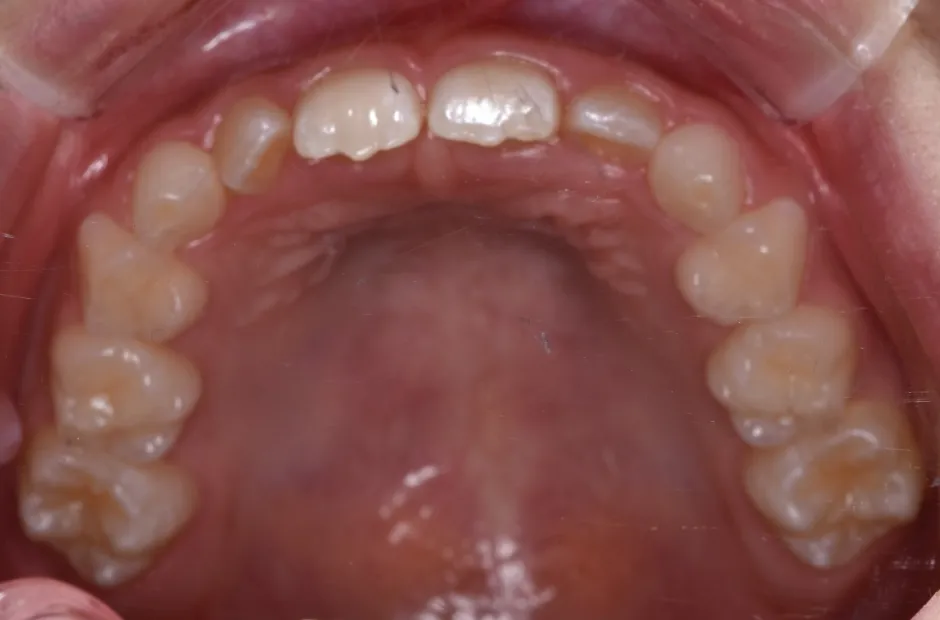

拡大床装置

叢生

| 診断名・主訴 | 叢生 |

|---|---|

| 年齢・性別 | 10歳・女性 |

| 治療期間・回数 | 2年半 |

| 治療に用いた主な装置 | 拡大床装置 |

| 抜歯部位 | なし |

| 治療費 | 30万円(税抜) |

| リスク・副作用 | 装置による違和感・疼痛・歯肉退縮・歯根吸収・虫歯のリスクなど |

治療前

治療中

治療後